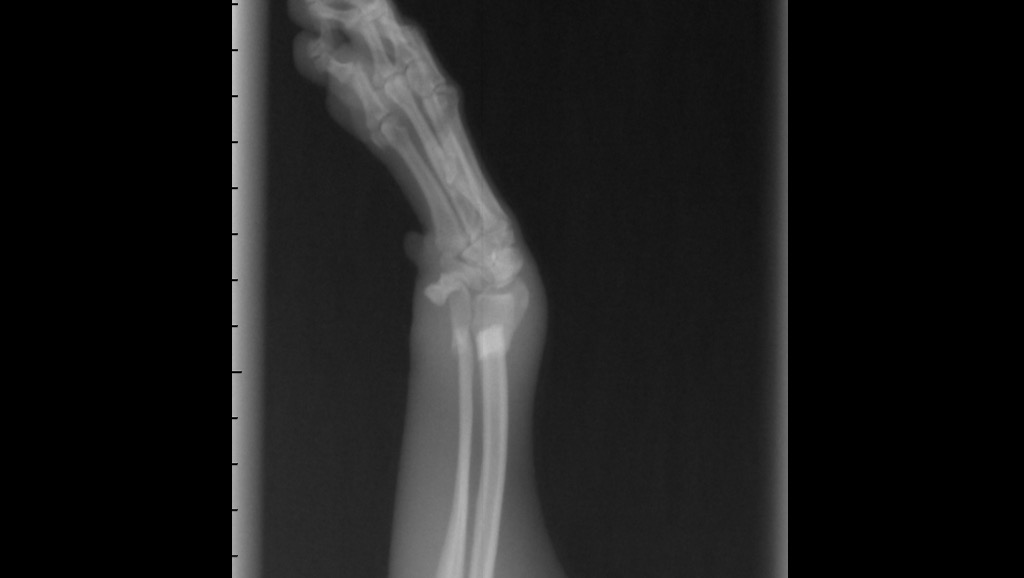

The vets called us and said they need to sedate her to do x-rays. She has two broken bones on her leg. Will attach photos of the X-rays.

The vets said she needs surgery, they sent the X-rays to a surgeon to give us a quote.

Estimate is $3,160.73 for Daisy's surgery where they need to put a plate in.